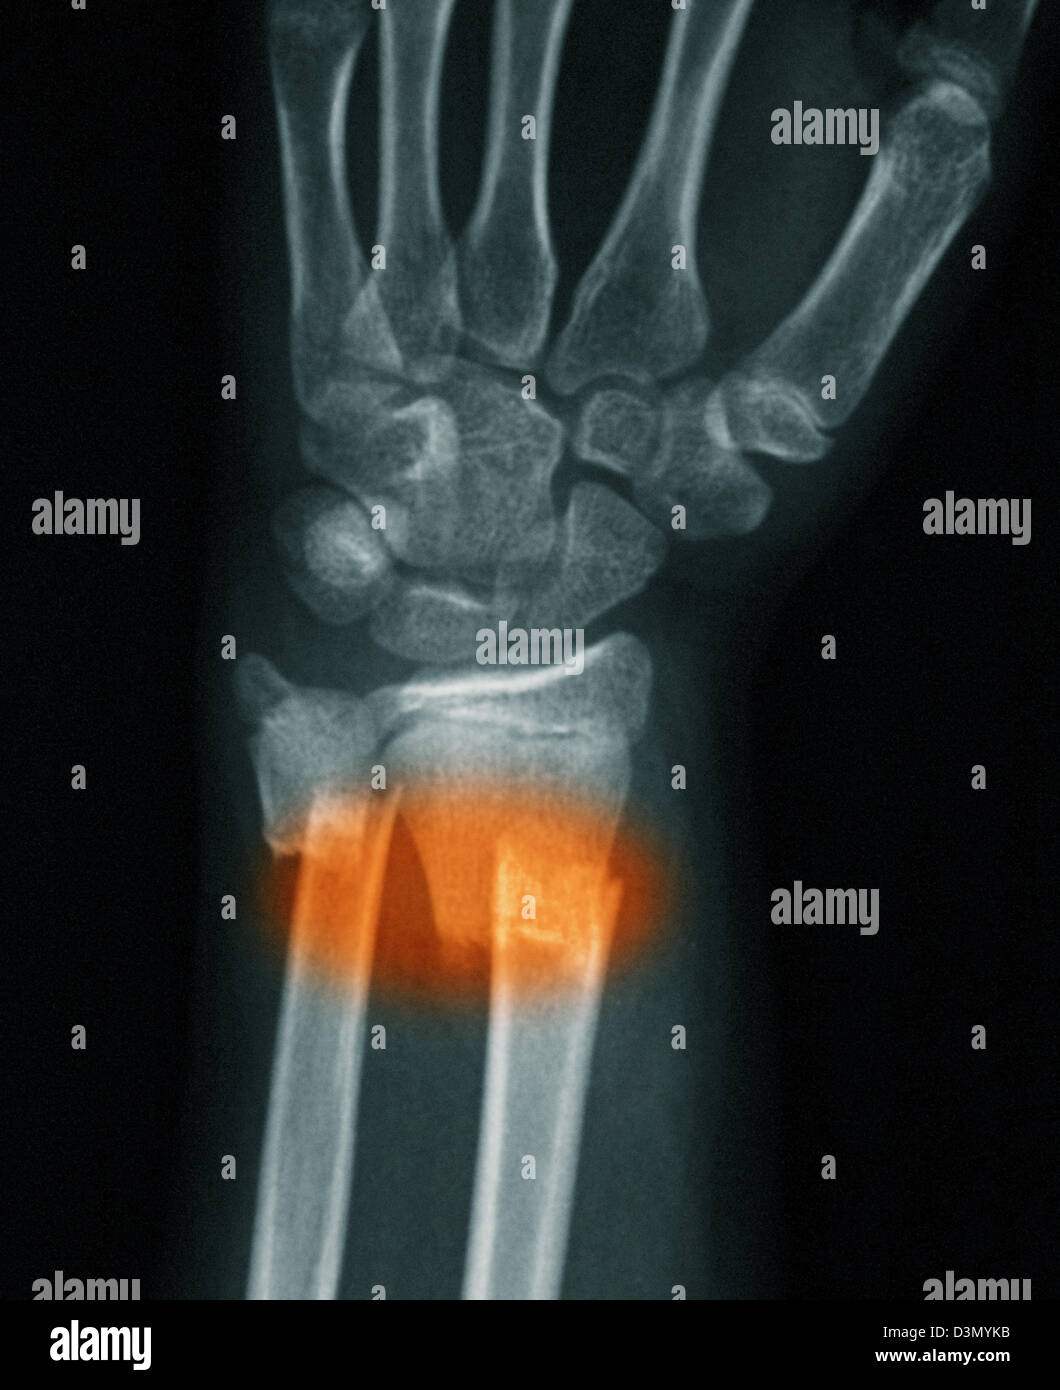

Cureus Isolated SalterHarris Type II Fracture of the Distal Ulna